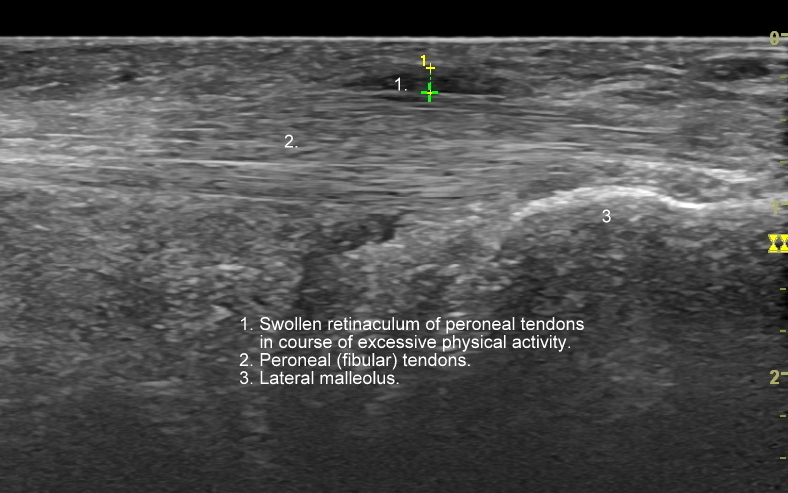

USG stawu skokowego i stopy

USG jest wysoce przydatną oraz metodą diagnostyczną pierwszego wyboru przy ocenie szeregu zmian chorobowych toczących się w obrębie stopy, w tym urazowych, przeciążeniowych, zapalnych, infekcyjnych, metabolicznych, czy nowotworowych. Przykładem najczęściej występującego urazu stopy, potocznie nazywanego skręceniem kostki występującego w wyniku inwersji stopy, jest naderwanie więzadła skokowo-strzałkowego przedniego (ATFL). Zmiany urazowo-przeciążeniowe dotyczyć mogą jednakże praktycznie każdego elementu. Dr Szczepański diagnozował w USG stopy m. in. takie patologie jak złamanie kości strzałkowej, złamanie trzeszczek, naderwania i zerwania ścięgien, czy przeciążenia troczków. W USG można ocenić również unaczynienie stopy, powikłania stopy cukrzycowej, zapalenie stawów w przebiegu dny moczanowej i reumatoidalnego zapalenia stawów, a także nowotwory stopy, w tym włókniaka rozścięgna podeszwowego (choroba Ledderhose’a).

USG łydki i podudzia najczęściej służy ocenie różnorodnych urazów, których sztandarowymi przykładami są łydka tenisisty, czy naderwanie / zerwanie ścięgna Achillesa. Dr Szczepański spotyka się w swojej praktyce również z szeregiem rzadkiego typu urazów i patologii takich jak przewlekły zespół ciasnoty przedziałów powięziowych, naderwania ścięgien zginaczy, przeciążenie troczków ścięgien, shin-splint, złamania przeciążeniowe kości, malformacje naczyniowe, zmiany nowotworowe, ciała obce, czy infekcje tkanki podskórnej, powięzi, a nawet mięśni.